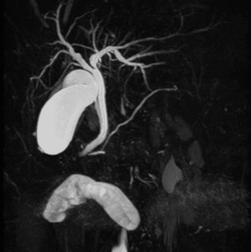

MRI部⾨

MRIとは、磁気共鳴画像診断装置(Magnetic Resonance Imaging)の略で、人体の中にたくさん存在している水の状態を、非常に強い磁石の力を用いて信号とし、コンピュータで処理して画像にする検査です。また、放射線を使用せずに検査を行うため被ばくがなく、造影剤を使用せずに血管を描出することが可能です。検査時間は約20 ~ 30分、造影剤を使用する検査では1時間程度かかることがあります。当センターでは3.0T装置と1.5T装置が導入されており、高分解能3D画像や非造影血管撮影などが可能です。このたび、2024年に1.5T装置のバージョンアップを行い、今までより短時間かつ高精度に検査を行えるようになりました。

MRCP画像

MRCP画像

頭部MRA画像

頭部MRA画像